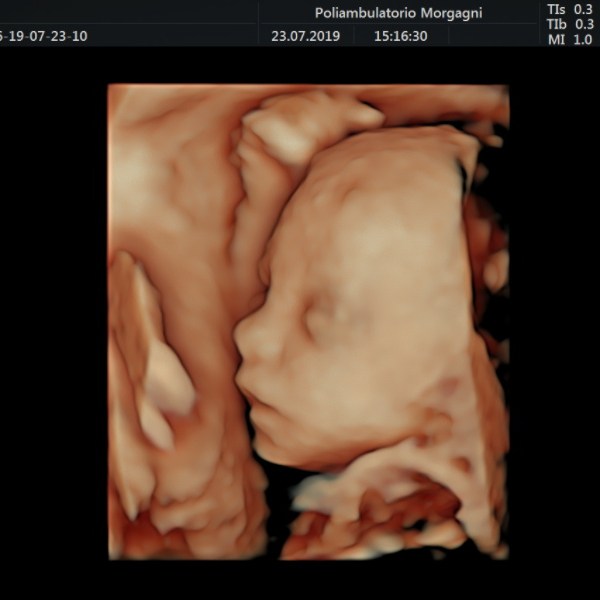

Il mese si conclude con l’ecografia di accrescimento da non eseguire troppo precocemente per ridurre il lasso di tempo fino al momento del parto.

Oltre la valutazione della biometria fetale, è importante controllare il benessere fetale con flussimetria a livello del cordone ombelicale e la quantità di liquido amniotico, vera cartina di tornasole del benessere fetale.